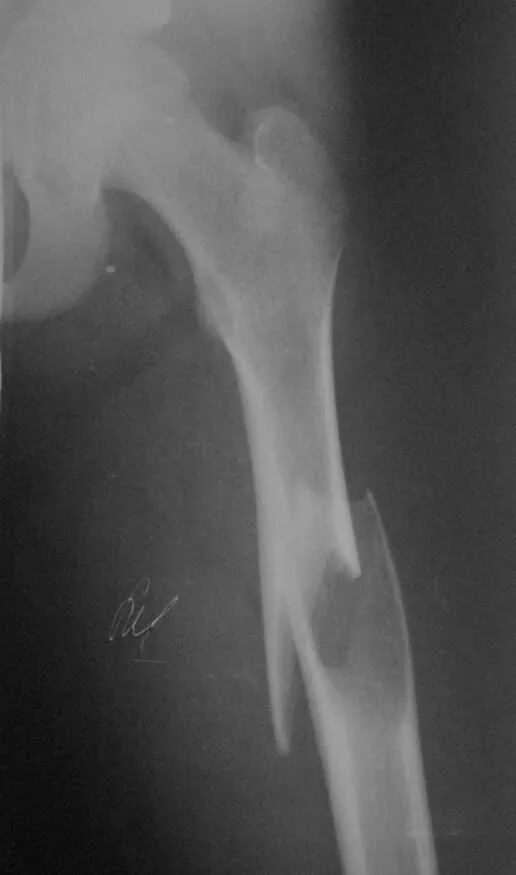

Патологический перелом бедра